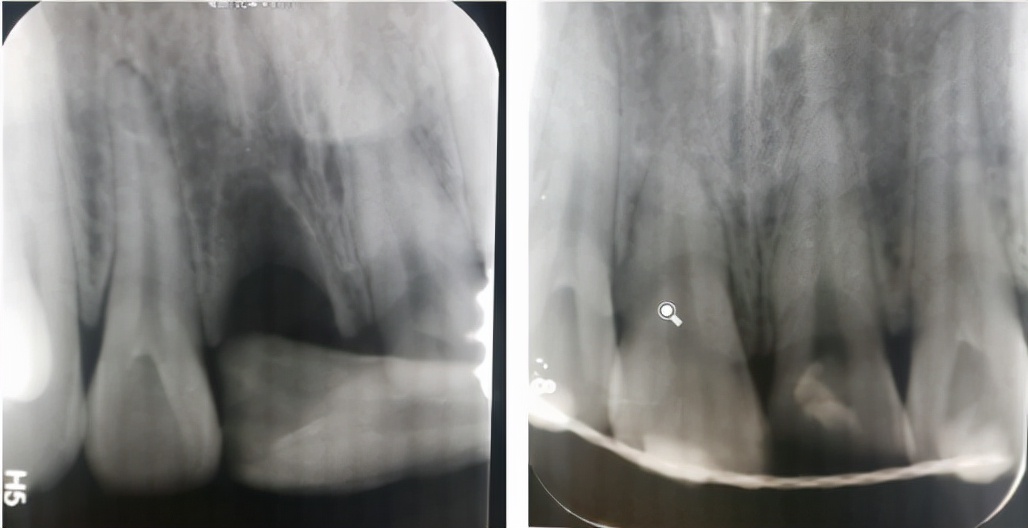

根折--根尖1/3

治疗方案:复位松动移位的断片,弹性夹板固定4周,定期检测折断线愈合情况,监测牙髓状态。牙髓坏死或感染则进行冠方的牙髓治疗。